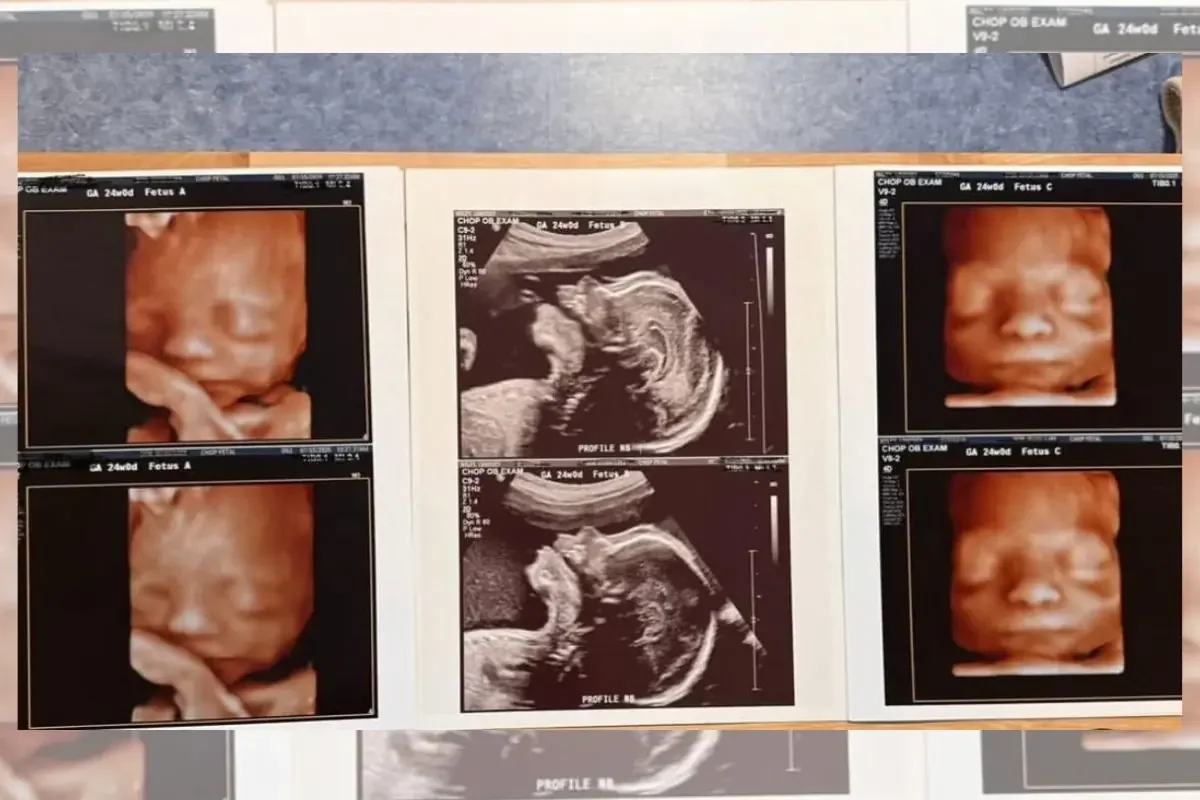

Lindsey Wiley, una madre estadounidense de 32 años y residente en Estados Unidos, vivió una sorprendente vuelta del destino. Con tres hijos varones de 5, 3 y 1 año y medio, ella y su pareja decidieron intentar una última vez ampliar la familia con la esperanza de tener una niña. Sin embargo, durante la primera ecografía, recibieron una noticia totalmente inesperada: estaban esperando trillizos, y todos eran niños.